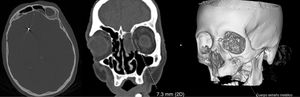

La analítica urgente mostraba leucocitosis (16100/mm3) con neutrofilia (89%), linfopenia (1000/mm3), elevación de fibrinógeno (4,72g/l), dímero-D (2645ng/ml), PCR (5,3mg/l), procalcitonina (0,8ng/ml) y ferritina (401,7ng/ml). Se realizó un TC craneal en el que se observaba dos artefactos metálicos en la región nasal izquierda y en el lóbulo frontal derecho, correspondientes con perdigones (fig. 1), una radiografía de tórax que mostraba un infiltrado intersticial en base derecha y una punción lumbar con líquido de aspecto turbio que mostraba 781 leucocitos/μl de predominio polimorfonuclear (88%), hipoglucorraquia (3mg/dl) e hiperproteinorraquia (4,61g/l). Se solicitaron hemocultivos, antigenuria de neumococo y Legionella que fueron normales y PCR de SARS-CoV-2 que resultó positiva. El estudio microbiológico del líquido cefalorraquídeo fue positivo para Streptococcus pneumoniae. Además, dada la sospecha de fístula de líquido cefalorraquídeo se realizó una TC facial de senos que confirmó la sospecha clínica.